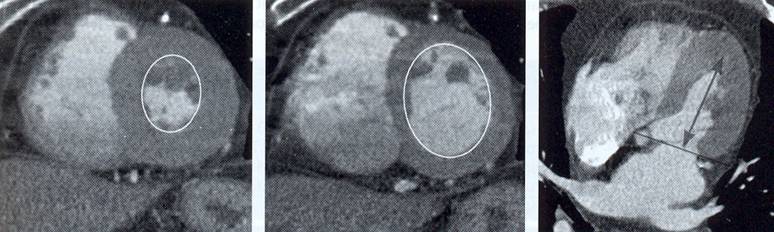

The non-invasive imaging modality of multi-detector computed tomography has dramatically evolved the last ten years and that is due to hardware and software developments. The newer generation of scanners allows increased spatial and temporal resolution that improves the clinical reliability giving further insights into the evaluation of coronary artery disease. Heart morphology imaging followed by studies of myocardial function and assessment of cardiac valves can be performed from the information derived from the data of the coronary artery examination. Also, the venous anatomy of the heart, coronary artery bypass grafts, stents, and cardiac tumors can be imaged and evaluated when necessary. For the beneficial use of this method, entrance criteria for different patient groups need to be set in order to allow improved outcome of multi-detector CT.